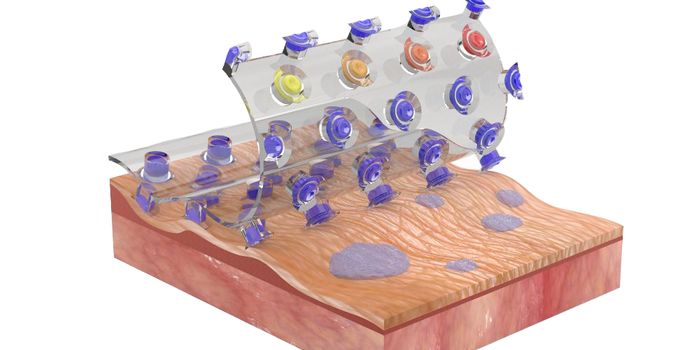

APR 01, 2021Clinical & Molecular DXWhat is e-skin technology? These wearable electronics are soft, flexible, and stick on to the surface of skin with a vas ...